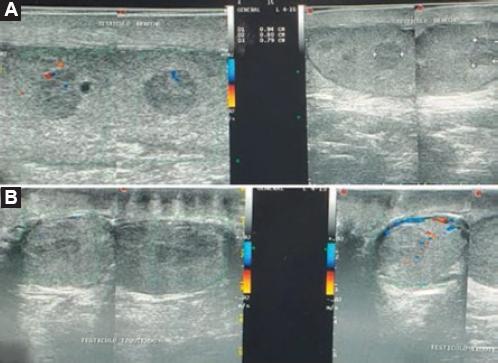

Figura 3 Ultrasonografía testicular. A: testículo derecho con imágenes hipoecoicas con respecto al perénquima, la mayor de 0.94 × 0.80 × 0.79 cm, sin aumento importante del flujo en la aplicación del Doppler. Se observan otras lesiones pequeñas, de 0.53 cm aproximadamente. B: testículo izquierdo con ecos heterogéneos, lesión hipoecoica de 1.83 × 1.21 × 1.61 cm, aumento de la vascularidad al Doppler.